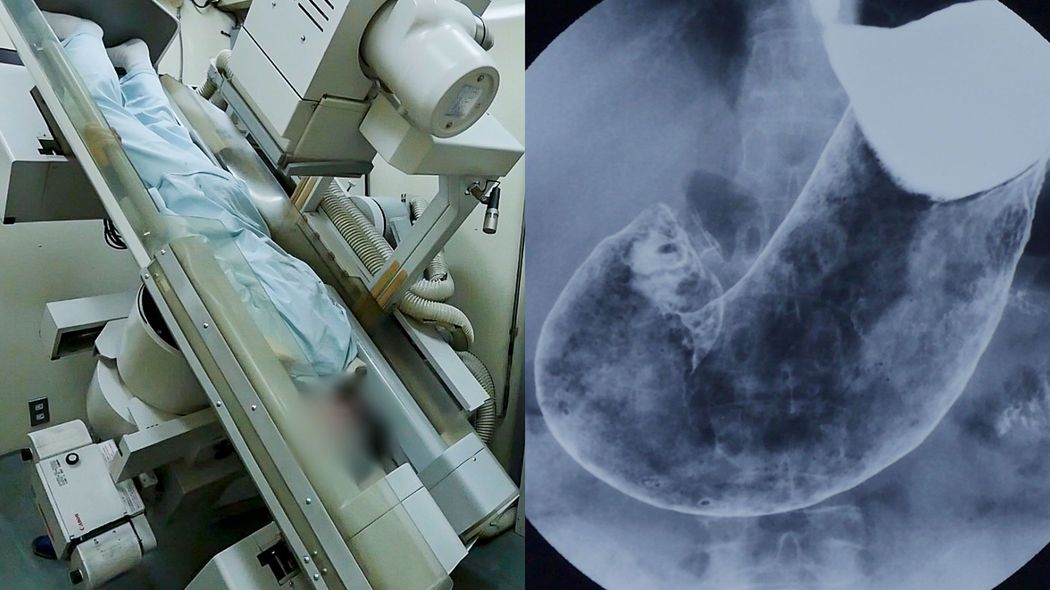

国が推奨している胃がん検診のうち、主流なのがバリウムX線検査だ。しかし、この検査には隠されたリスクが多いという。ジャーナリスト・岩澤倫彦さんの著書『がん「エセ医療」の罠』(文春新書)より、バリウム検査を受けて九死に一生を得た61歳男性のエピソードを紹介する――。